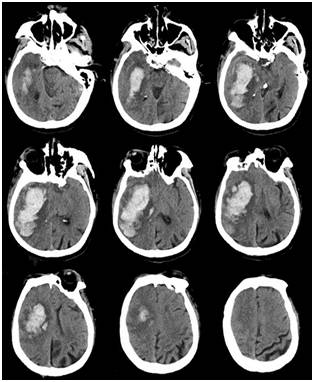

急查血常规示:Hb128g/L,PLT58×109/L,HCT36.5%(考虑强力脱水因素,上述数值有虚高可能)。凝血功能示:PT12.3 s、APTT26.10 s、FIB1.68 g/L。血栓弹力图示:MA46.1mm,提示血小板功能低下。生化示:白蛋白33.6g/L,总胆红素43.4μmol/L,间接胆红素35.5μmol/L。头颅CT示:右侧基底节区脑出血,量约70ml,中线结构左移,环池显示不清(Fig.1)。腹部CT示:肝硬化、脾大。

Fig.1入院时头颅CT示右侧基底节区脑出血